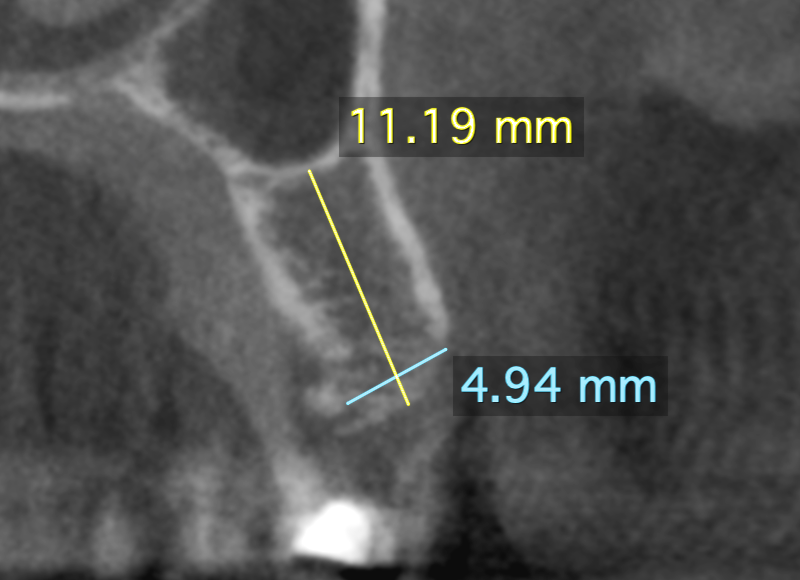

Consultation services for other doctors who utilize CBCT, CT or MRI scans in their patient care. Click on below images to download some sample reports.